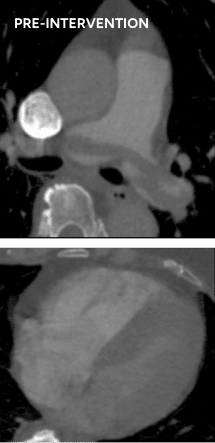

5.

Bilateral PE case

RESCUE protocol – total of 14mg r-tPA (7mg per lung)